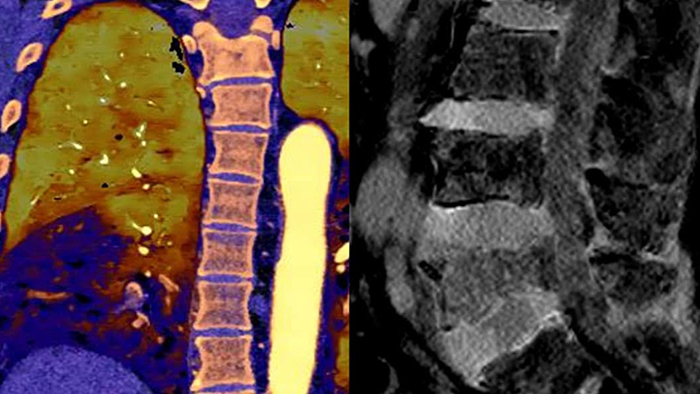

Unlike traditional CT images, spectral-detector CT images capture spectral information 100% of the time —without special planning or set-up. That means you can analyze the spectral data in any image retrospectively, using a variety of spectral viewing tools. You can, for example, adjust the monoenergetic level or get Zeffective maps.

Move the slider to reveal spectral results when compared to conventional CT.

Conventional CT Spectral result

Spectral detector simultaneously absorbs and differentiates high and low energy from a single polyenergetic X-ray beam. Spectral results are acquired within a single scan without the need for special modes.

Detector-based spectral CT simultaneously absorbs high and low energies in the same time and space.